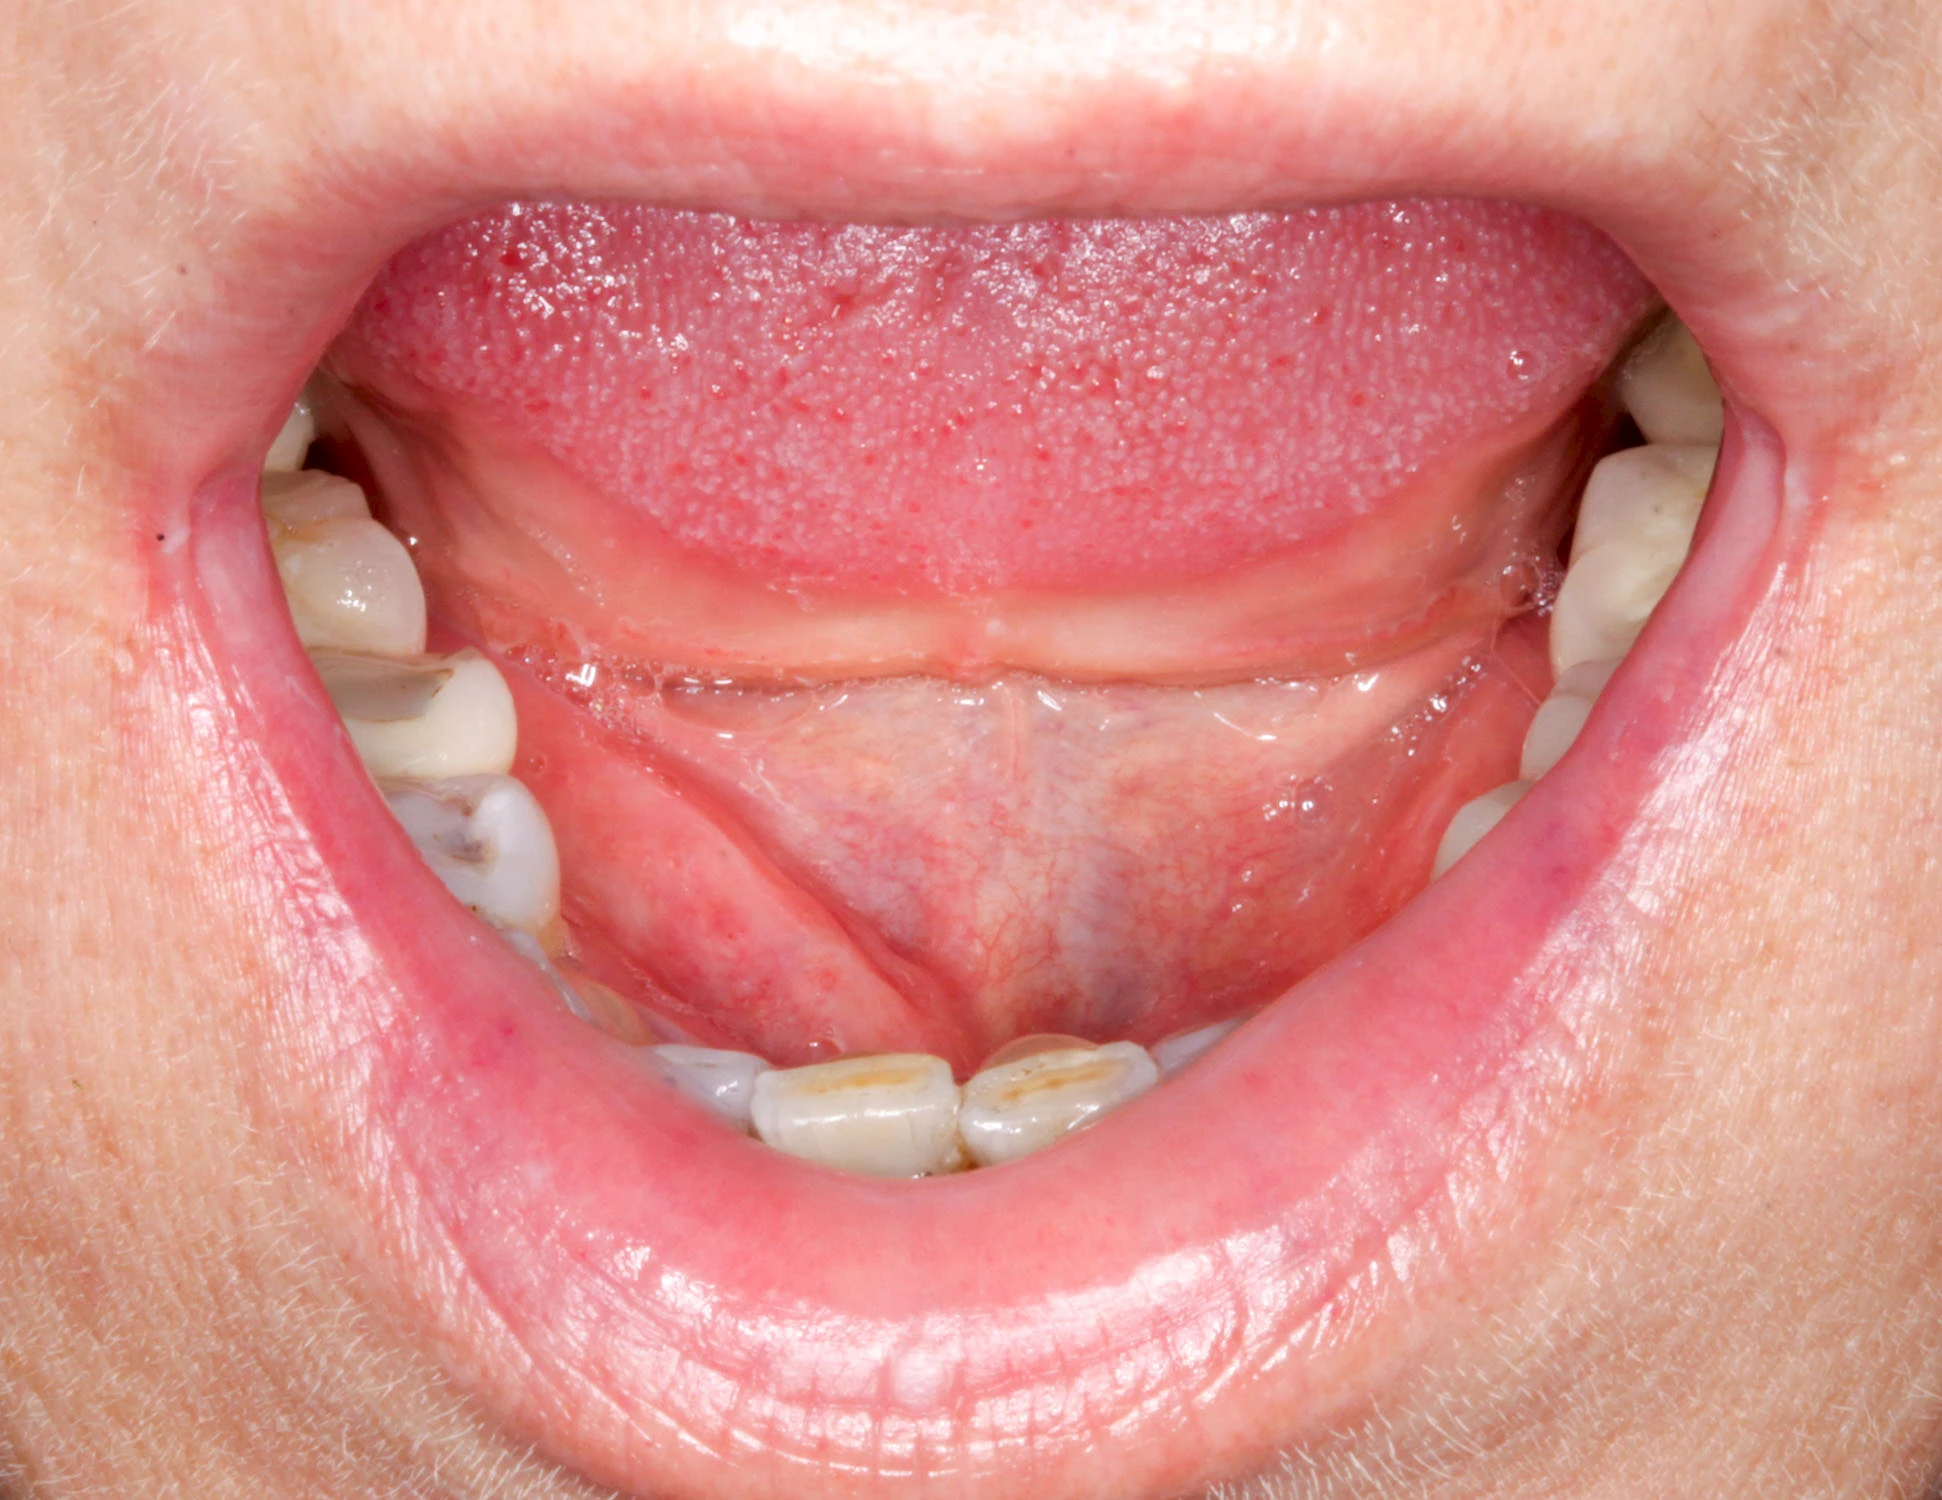

Speicheldrüsenzyste

Eine Speicheldrüsenzyste (Speicheldrüsenretentionszsyte) kann als Schwellung oder Auftreibung meist im Bereich der größeren Ausführungsgängen auffallen, wenn z. B. ein Speichelstein den Speichelfluss behindert. Vor allem bei den Mahlzeiten, wenn der Speichelfluss angeregt wird, nimmt die Auftreibung oder Schwellung schmerzhaft weiter zu. In der Regel ist die Unterkieferspeicheldrüse (Glandula sublinugalis) betroffen. Man spricht dann auch von einer Frosch- bzw. Fröschleingeschwulst (Ranula). Bringt sanftes Massieren der Schwellung bzw. Auftreibung keine Verbesserung, sollte ein Arzt oder Zahnarzt hinzugezogen werden